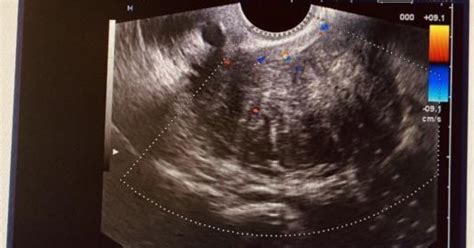

Diagnosticul fibromului uterin se bazează pe examenul clinic și investigațiile imagistice, care permit medicului să stabilească numărul, dimensiunea și localizarea fibroamelor. Acestea includ examenul ginecologic, ecografia transvaginală sau abdominală, precum și, în cazuri complexe, rezonanța magnetică (RMN) pelvină sau histeroscopia. O hemogramă completă poate fi indicată pentru a depista o eventuală anemie cauzată de sângerările uterine abundente. De asemenea, pot fi recomandate analize hormonale pentru o evaluare mai amplă.

Prezența fibromului nu înseamnă automat că sarcina nu este posibilă sau că trebuie operat urgent. Totul pornește de la informare și de la un consult la timp. Fibroamele care pot afecta real fertilitatea sunt cele situate în interiorul cavității uterine, deoarece pot interfera cu implantarea sarcinii. Mărimea și localizarea sunt cele care fac ca fibromul să afecteze fertilitatea. Marimea fibromului uterin poate varia de la cea a unui bob de mazăre, până la una ce o depășește pe cea a unui grapefruit.

Cifrele arată că între 5% și 10% dintre femeile care se confruntă cu infertilitatea sunt diagnosticate cu fibrom. În cazuri rare, fibroamele pot îngreuna implantarea ovulului fecundat în uter sau deplasarea spermatozoizilor către ovul. Fibromul submucos, care se dezvoltă din peretele uterin spre cavitate, poate bloca o trompă uterină și astfel face concepția mai dificilă. Totuși, majoritatea femeilor cu fibrom uterin pot rămâne însărcinate.